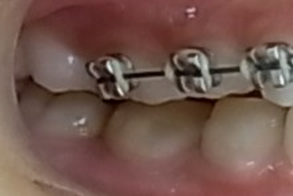

初診時乳臼歯にレジンを盛る事で咬み合わせの高さを治療していきます。

乳臼歯にレジンを盛る事で咬み合わせの高さを改善する方法の説明。

乳臼歯にレジンを盛る事で第一大臼歯の咬み合わせに隙間が出来ました。

約2か月で隙間が埋まり第一大臼歯が咬み合いました。

上顎から矯正装置を装着していきます。